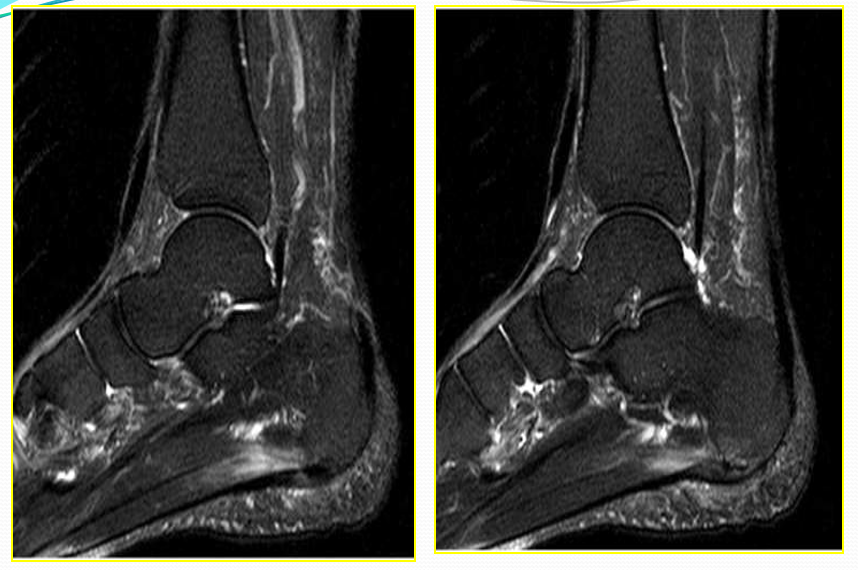

距腓前韧带撕裂

病因病理机制:

• 最脆弱的外侧韧带,也最先断裂

• 内翻内旋伴跖屈

• 距腓前韧带撕裂致内旋受限

• 临床表现为前外踝疼痛,活动受限